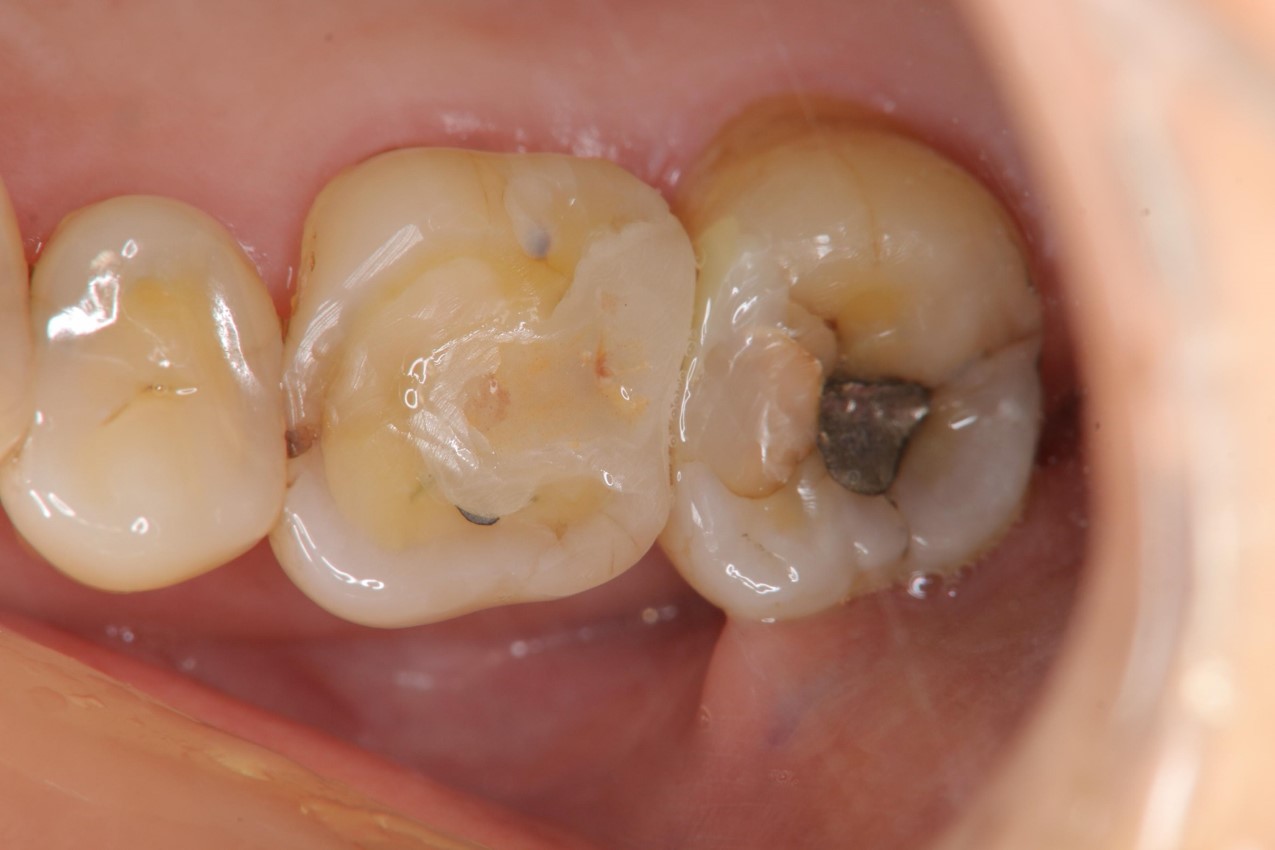

治療前,因磨耗,導致原瓷塊斷裂

治療前,牙髓仍完整